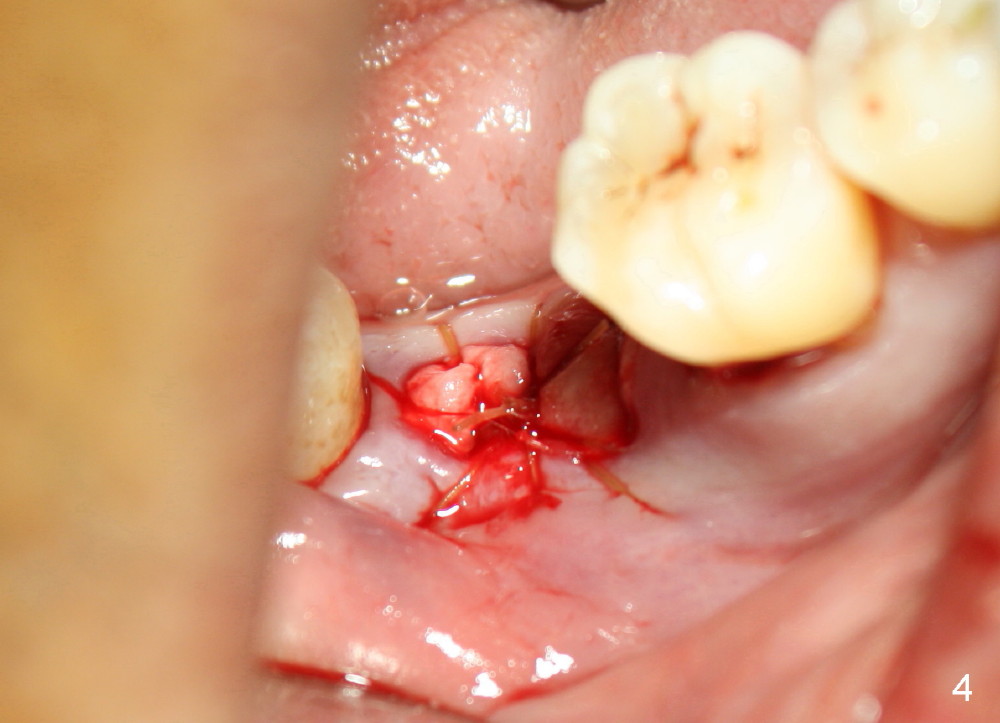

Mobility and pain associated with the lower right 2nd molar (Fig.1 *) are chief complaints from a 62-year-old man. Infiltration anesthesia allows for extraction and debridement of the socket, but not osteotomy with drills due to inability to achieve complete anesthesia. Because of limited bone height (Fig.1 red line), block anesthesia is not administered on purpose. Immediate implant is aborted; socket preservation is to be done. In short, pain control is a limiting factor for immediate implant. If pain is chief complaint prior to extraction, possibility of not performing immediate implant should be informed to the patient prior to the surgery. The patient should take antibiotic several days preop.